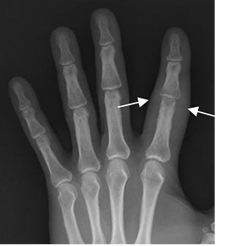

Un hallazgo importante que ocasiona la AP, es la prominencia de los tejidos blandos. Puede afectar todo un dedo, dando la apariencia de “dedo en salchicha”. (1). (Fig 54 A).

Fig 54 B. Artropatía por psoriasis.

Rx AP. “Dedo en salchicha”, por compromiso de los tejidos blandos.